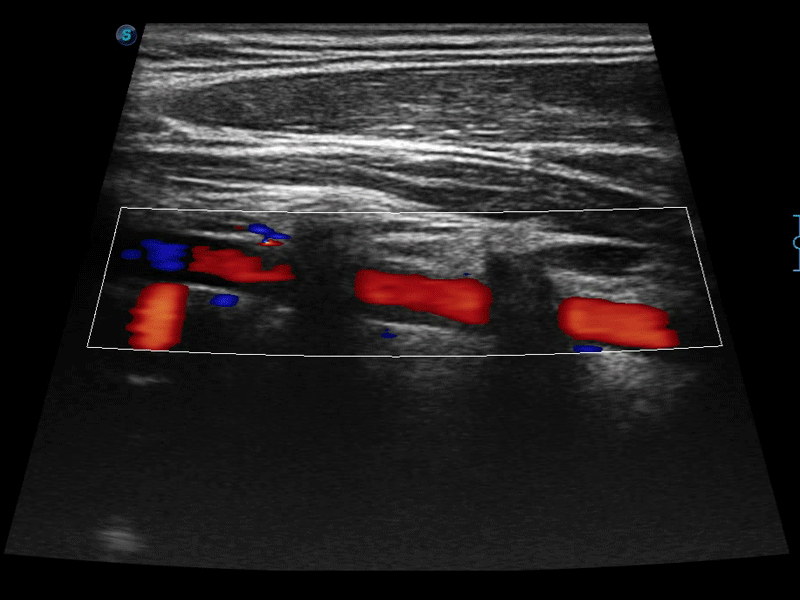

高分辨率血流成像技术提高了对低速血流信号的检测能力。在提高空间分辨率的同时,也克服了血流外溢现象,为用户提供更加真实的血流动力学信息。

通过色彩血流和实时宽景相结合,可观察到完整的静脉或动脉的血流,方便医生检查。实时扫查过程中,如有任何操作失误也可以很容易地进行回扫擦除,而不会中断扫查。